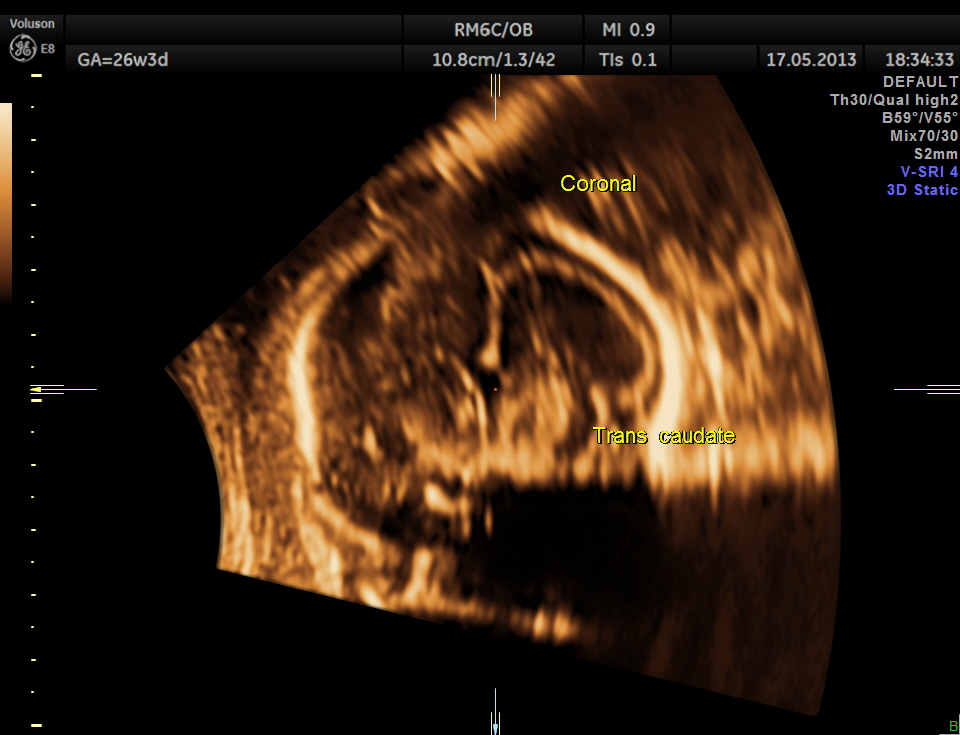

The following are 3 D reconstructed sagittal and coronal images .